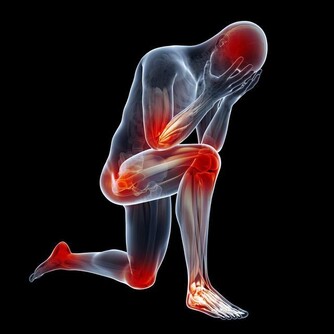

改善肝臟功能,有助於抵禦風濕性疾病和痛風